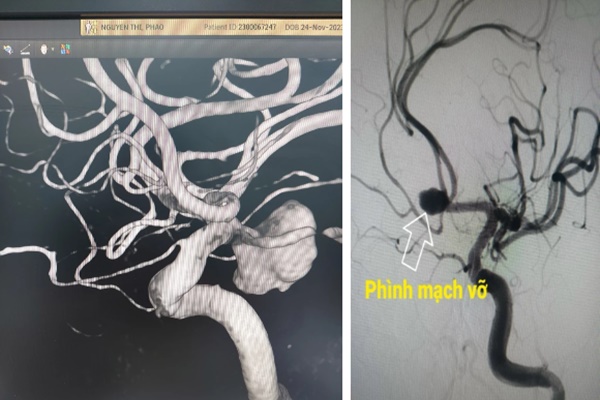

Hình ảnh một số trường hợp vỡ phình động mạch não gần đây:

Vỡ phình động mạch não có thể gặp ở mọi lứa tuổi, thường gặp nhất là từ 40 – 60 tuổi và có xu hướng tăng lên ở người trẻ tuổi. Đây cũng là một trong những nguyên nhân thường gặp gây đột quỵ xuất huyết ở người trẻ. Căn bệnh nguy hiểm này gây ra khoảng 10 – 15% trường hợp bệnh nhân tử vong trước khi đến viện và khoảng 50% tử vong trong tháng đầu tiên sau khi bị vỡ phình mạch.